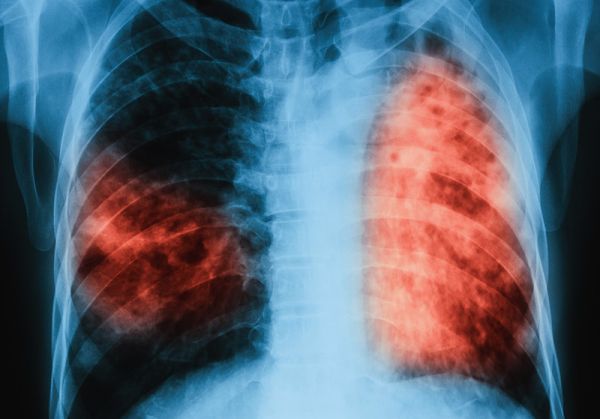

Характерно за латентната туберкулоза е, че тя преминава безсимптомно и при инфектираните лица не се наблюдават клинични, микробиологични или рентгенологични данни за наличие на активно туберкулозно заболяване. Макар че хората с латентна форма на заболяването не проявяват явни симптоми на активна туберкулоза и не са носители на заразата, те могат да бъдат окачествени като постоянни резервоари на инфекцията. При някои от тях има повишен риск от развитие на активно заболяване и те могат да станат източник на инфекция, обясни д-р Давчев.

Бързото диагностициране и адекватното лечение на болните с активна туберкулоза са от първостепенно значение за осъществяване на контрол над коварното заболяване. Също така трябва да се проследи и състоянието на лицата, които са били в контакт с болния от активна туберкулоза. Ранното откриване гарантира не само излекуване на вече заразените, но и прекъсване на веригата на предаване на болестта, подчерта д-р Веселин Давчев.